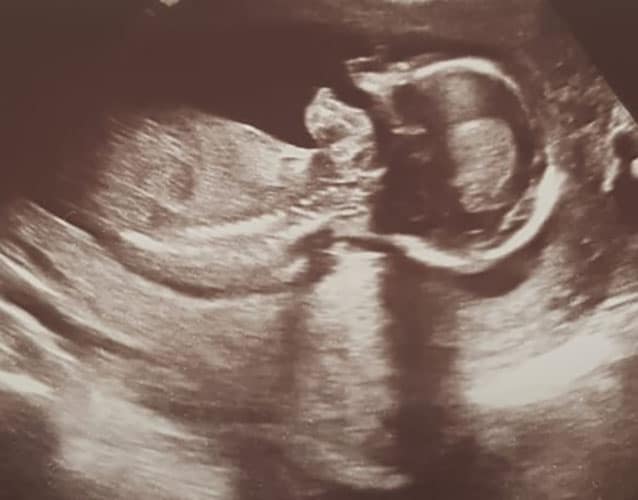

Ultraschallbilder aus dem 2. Trimester (13. bis 28. SSW)

Im 2. Trimester bekommt man oft die schönsten "Ganz-Körper" Ultraschallbilder. Das Baby ist nun so groß, dass man alles gut erkennen kann und noch nicht zu groß, so dass es noch ganz auf das Bild passt. In dieser Zeit lässt sich meist das Geschlecht bestimmen, wobei manche Babys es einfach nicht preis geben wollen und sich immer so drehen, dass man nichts erkennen kann.